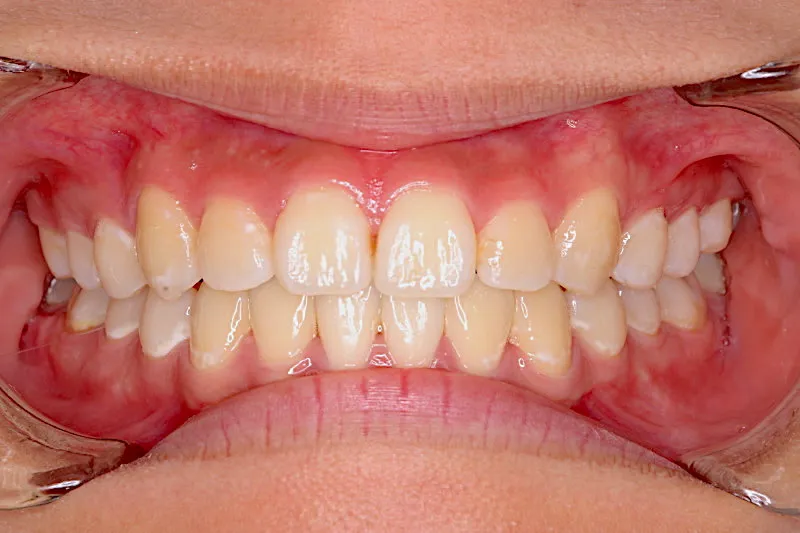

治療終了後

治療回数57回、6年9ヶ月の治療期間で矯正治療を終了しました。

主訴が改善され、ご満足頂きました。